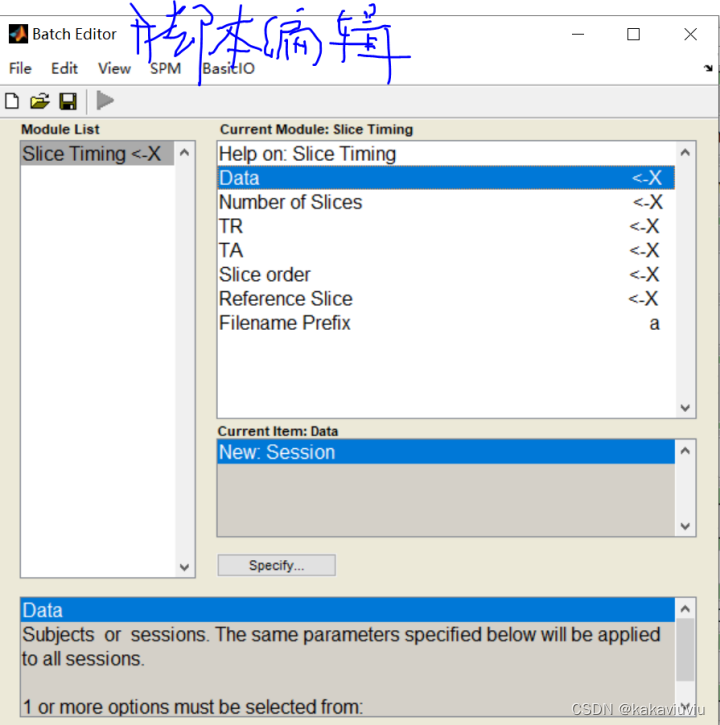

(2)第二步是A:时间层校正,

打开spm,点击slice timing--data--点击session

导入进nii文件,注意把右下角的1换为inf(无限的意思),然后右键--select all

(可以提前把matlab的路径设置成存放文件的路径,这样方便选择)

frame:1 --第一帧的图像 ,一般写成inf(无穷,可以包含所有的图像)

filter旁边的白色长空格可以输入文件名来筛选文件

选完点done

扫描层数:33层

填写TA

扫描顺序:1是首项,2是步长,33是尾项;两个等差数列之间用空格隔开(会自动判断是否结束)。翻译过来就是1 3 5 7层 ... 2 4 6 8层...这样的扫描顺序

参考层:中间层的层数(第33层)

填好了然后点绿色的符号开run!